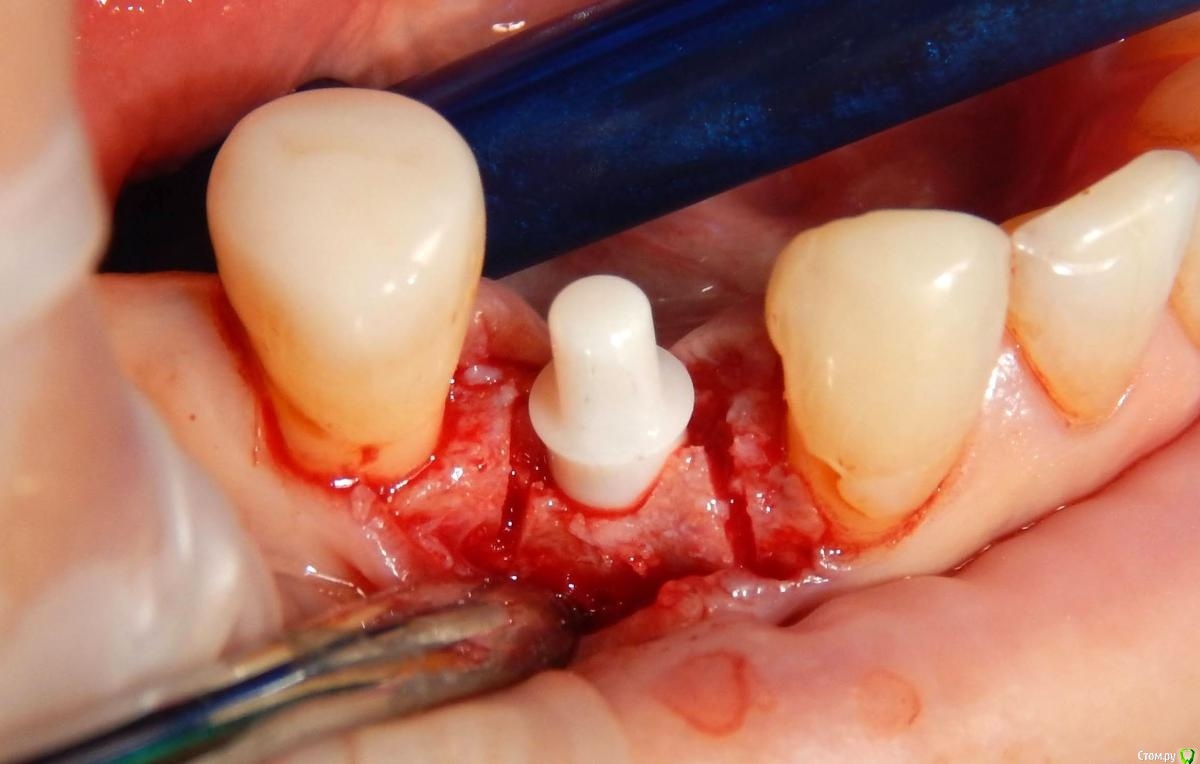

Astronaft Опубликовано 24 января, 2021 Поделиться Опубликовано 24 января, 2021 (изменено) Одиночный цирнокиевый имплантат и расщепление без графта. Пациентка:тонкая хрупкая женщина 55 лет, сконцентрированная на своем здоровье, в некоторой мере мнительная.всегда тяжелые заживления после удалений (по опросам)есть результаты Клиффорд теста (такая книжка под 200 страниц с in vitro аллерго-пробами на все известные материалы) Поставленная цель:только цирконий Мне было интересно найти вариант найболее приемленый пациентке и мне. С минимом хирургического риска и риском сожаления пациентки про выбор костного материала. Во-первых, я не использую аллографты - философски, чужие протеины, неприятный запах - просто основываясь на своем мнении.Во-вторых, мнительные пациенты склонны "пойти и почитать" до или потом и как следствие внушить себе вещи которых может и не было. Но по скольку мысль материальна... Все обсудил заранее.План: ридж сплит (расщепление), имплантат без графта, свободный СТ графт; если случается вестибулярная рецессия - пилим зирконий во рту. Ридж сплит сделан пьезотомом - крестальный и вертикальные пропилы на глубины около 8-10мм.Пилотное сверло.Развдвинул кость остеотомами от 1.6мм до 3.5мм в диаметре.Очень мягкая кость - напомнила мегкую максиллу плотности ногтевой пластинки вестибулярно.Имплант встал легко, но торк 40нсм. СТ графт из области 18. Деэпителизирую скальпелем уже потом. Тут интересно отметить, что я перестал боятся ошметков эпителия.Пончо сверху имплантата (а-ля шашлык Карлоса).Швы. PTFE всегда хорош. 12 недель.Красивая десна.Периотест -5.8 - отличный результат.Оттиск. Циркониевая коронка симметричная другой стороне. Изменено 24 января, 2021 пользователем Astronaft 19 Ссылка на комментарий

Astronaft Опубликовано 25 января, 2021 Автор Поделиться Опубликовано 25 января, 2021 Спасибо.День операции, 12 недель, день цементировки. 3 1 Ссылка на комментарий